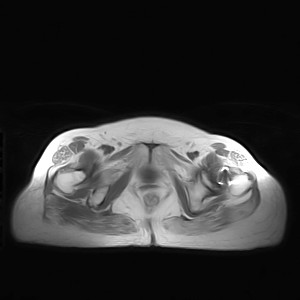

图像太差了 1、右侧臀肌旁脓肿? 建议增强 2、左侧股骨头坏死并半脱位

1、左侧股骨头坏死并髋关节半脱位;

2、右侧臀肌感染,(可能褥疮所致)